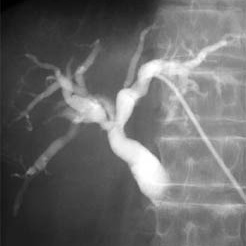

Colangiografia percutanea. 877603 Idime

Bogotá, Bucaramanga |

$270000 |

IDIME. Instituto de Diagnóstico Médico. Código de Convenio : 8915

BOGOTÁ

Sede Norte: Autopista Norte No. 122 – 68

BUCARAMANGA

Carrera 27 No. 30 - 15 Segundo Piso Hospital Universitario Los Comuneros

INCLUYE MEDIO DE CONTRASTE